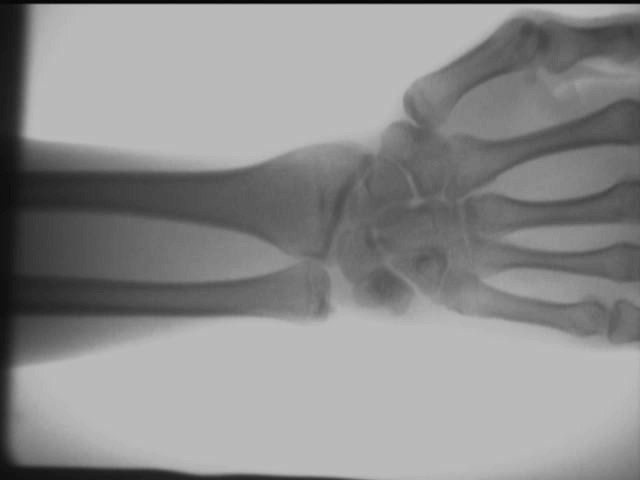

Ortopeedilise röntgendetektori kohapealse testimise mõju diagramm

Käe hüppeliigese efekt

Ülaltoodud testitulemused saadakse kohapeal, kasutades AS-C200kaasaskantav röntgeniaparaat